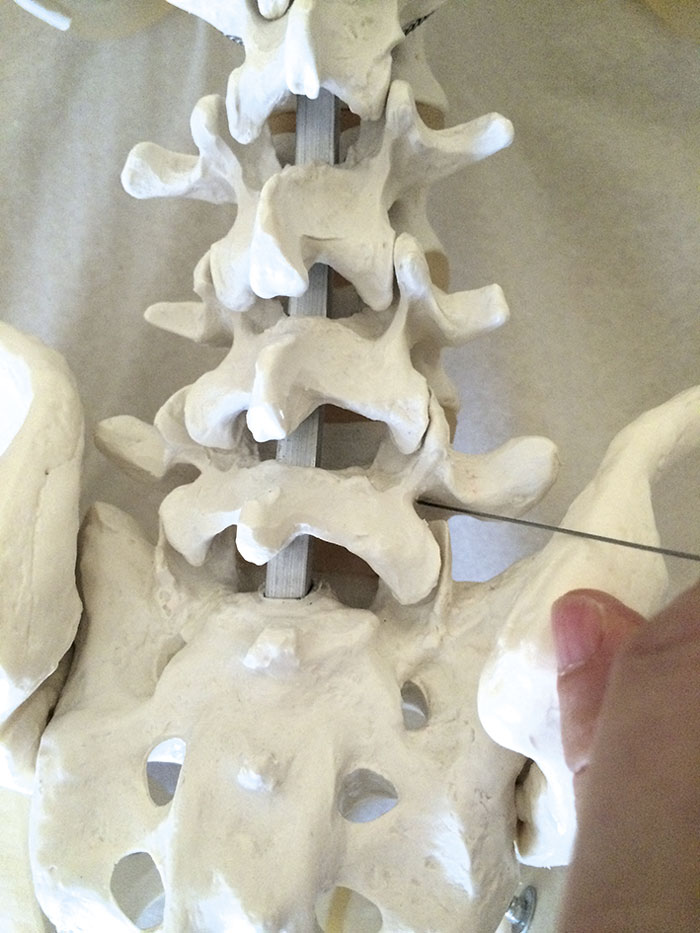

Tekniskt skiljer man på transforaminala injektioner där man från en dorsolateral riktning på nålen placerar spetsen i närheten av nervroten strax innanför foramen (Figur 1). Injektionen sker därmed i nära anslutning till gangliet, och effekten riktas mot en enskild nervrot.

Figur 1. Nålspetsens placering vid transforaminal injektion.